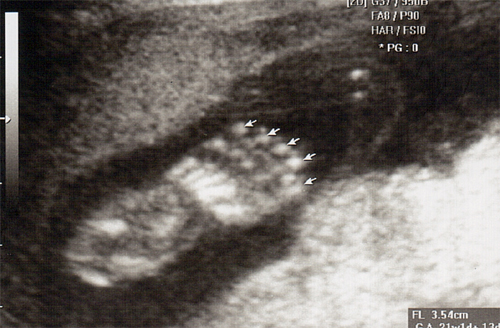

강아 ^^ 21주 강이의 정밀 초음파를 봤어 일반 초음파 보다는 더 정밀하게 나오더라구 엄청 커버린 강이가 한눈에 보이지 않을정도로 이제는 초음파 기계가 작아 보이더라..